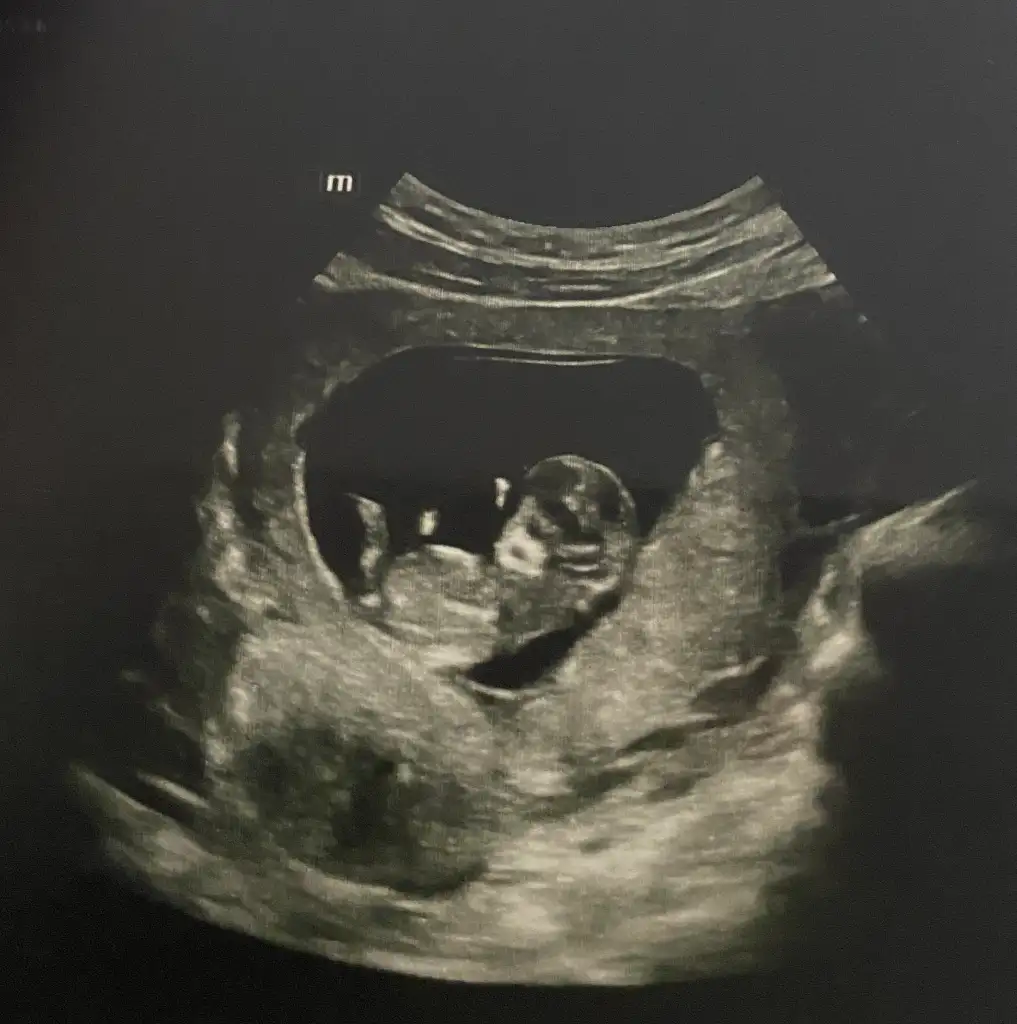

Yüz üstü durmuş sankiAy benimde 12 +1 bana da tahminde bulunabilir misiniz![]()

Evet yüz üstü yatıyor o yüzden doktorda bişey diyemedi belki sizin bi tahmininiz vardır diye sormak istedimYüz üstü durmuş sanki![]()

Belli oldu mu cinsiyetinizBende sizinle ayniyim 13+2 cuma günü gideceğim bakalım ne diyecek

Yok canım ya inşallah bir dahaki sefere düzgün pozisyon alır minik kuşEvet yüz üstü yatıyor o yüzden doktorda bişey diyemedi belki sizin bi tahmininiz vardır diye sormak istedim![]()

Benim attığımı da tahmin eder mısınız 11+5Bariz erkek görüyorum, sağlıcakla gelsin inşallah![]()

Erkek görüyorum sağlıcakla gelsin inşallahBenim attığımı da tahmin eder mısınız 11+5